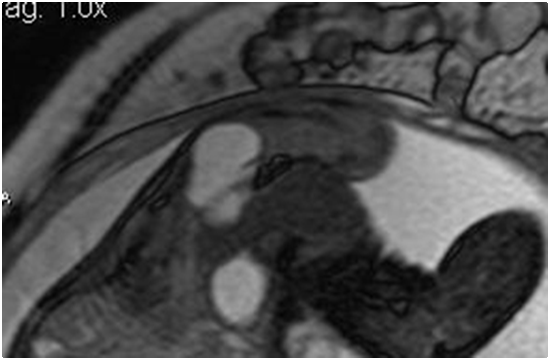

Hình 4. Cắt lớp bằng cộng hưởng từ khẳng định bản chất SCT, không ghi nhận xâm lấn vùng trực tràng-sinh dục |

Thai phụ 32 tuổi, Para 1001 được chuyển đến Đơn vị Chẩn đoán tiền sản Bệnh viện Từ Dũ vào 33 tuần thai sau chẩn đoán nghi ngờ thoát vị màng não-cột sống chẻ đôi. Siêu âm hình thái học tại đơn vị chúng tôi ghi nhận một khối u vùng xương cùng, dạng nang, phân bố mạch máu trung bình, kích thước 59x27mm. Với nghi ngờ bản chất u là SCT, thai phụ được tiến hành chụp cộng hưởng từ (MRI). Chuỗi xung sử dụng diffusion, T1w, T2w haste, trufish 3 mặt cắt axial, coronal, sagital FOV 350x350mm, độ dày lát cắt 3-5mm và hình ảnh MRI khẳng định u SCT, không dấu hiệu xâm lấn vùng trực tràng-sinh dục. Các tiêu chuẩn hình ảnh khiến u được xếp loại nhóm A (Benachi). Để đề phòng nguy cơ phải can thiệp lấy thai non tháng, thai phụ được chủ động dùng Betamethasone cho mục đích trưởng thành phổi thai. Thai kì được theo dõi tại đơn vị chẩn đoán trước sinh mỗi 2 tuần, không ghi nhận gia tăng đáng kể kích thước khối u cũng như các thay đổi về nước ối, Doppler velocimetry và chỉ số tim-lồng ngực. Thai kì được kết thúc vào 38 tuần bằng phương pháp mổ lấy thai vì lo sợ khối u vỡ trong quá trình chuyển dạ (ngôi mông). Thai nhi cân nặng lúc sinh 3.500g, điểm Apgar là 8 ở 1 phút và 9 ở 5 phút. Khám trẻ sau sinh ghi nhận khối u vùng xương cùng-cụt, kích thước 60x60mm và không tìm thấy thêm khiếm khuyết bẩm sinh nào khác. Sau xuất viện ngày 5, bé được khám và chụp CT scan tại Bệnh viện Nhi đồng 2; kết quả CT scan chẩn đoán phân biệt với thoát vị màng não tủy vùng xương cùng. Phẫu thuật tiến hành vào ngày thứ 19 sau sinh, không biến chứng xảy ra và giải phẫu bệnh khẳng định bản chất teratoma trưởng thành của u.

Việc ứng dụng MRI thai đem đến nhiều đánh giá quan trọng trong chẩn đoán và tiên lượng các bất thường mô mềm trên thai. Đối với SCT ở thai, vì bóng âm tạo ra do xương cùng của thai, vai trò siêu âm trở nên giới hạn, đặc biệt đối với phần u phát triển trong vùng chậu, nhất là trong 3 tháng cuối. MRI khi này có thể cung cấp thêm nhiều thông tin về kích thước cũng như sự chèn ép, xâm lấn các cơ quan lân cận của u: đẩy lệch đại tràng, chèn ép đường niệu dưới, thậm chí trật khớp háng, vốn không thể đánh giá được chính xác bằng siêu âm. Ngoài ra, khi các thành phần trong u có tính phản âm (echogenicity), MRI còn giúp phân biệt được bản chất mô là đặc hay xuất huyết trong u. Các chi tiết này có thể góp phần vào chỉ định cách sinh cho thai, nghiêng về hướng mổ lấy thai chủ động khi u chứa nhiều phần đặc hoặc phức tạp [4,14 ].